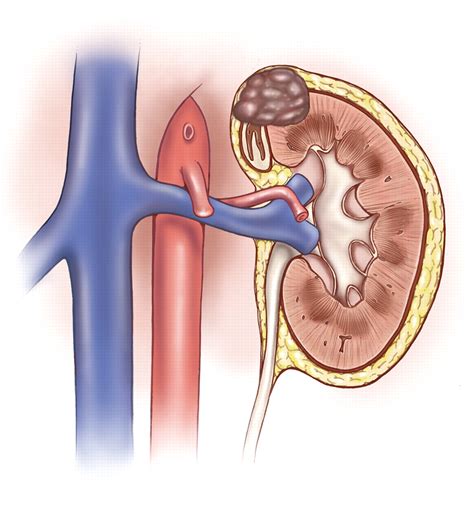

Stage III kidney carcinoma is more advanced and may involve one or more of the following:

• The tumor has grown into nearby structures, such as the adrenal gland or major blood vessels.

• Cancer has spread to nearby lymph nodes.

• There is evidence of tumor thrombus in the renal vein or inferior vena cava.